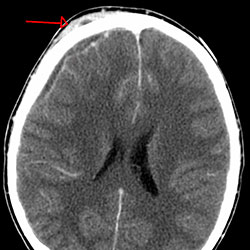

The 16-month-old child was admitted to a pediatric ICU in Arkansas in September 2023 after a three-day history of fever, vomiting, decreased oral intake, decreased activity and new onset of altered mental status. Naegleria spp., a free-living ameba that is found in warm fresh water and soil, was identified two days after hospitalization. Despite treatment, the child’s condition worsened, and the patient died.